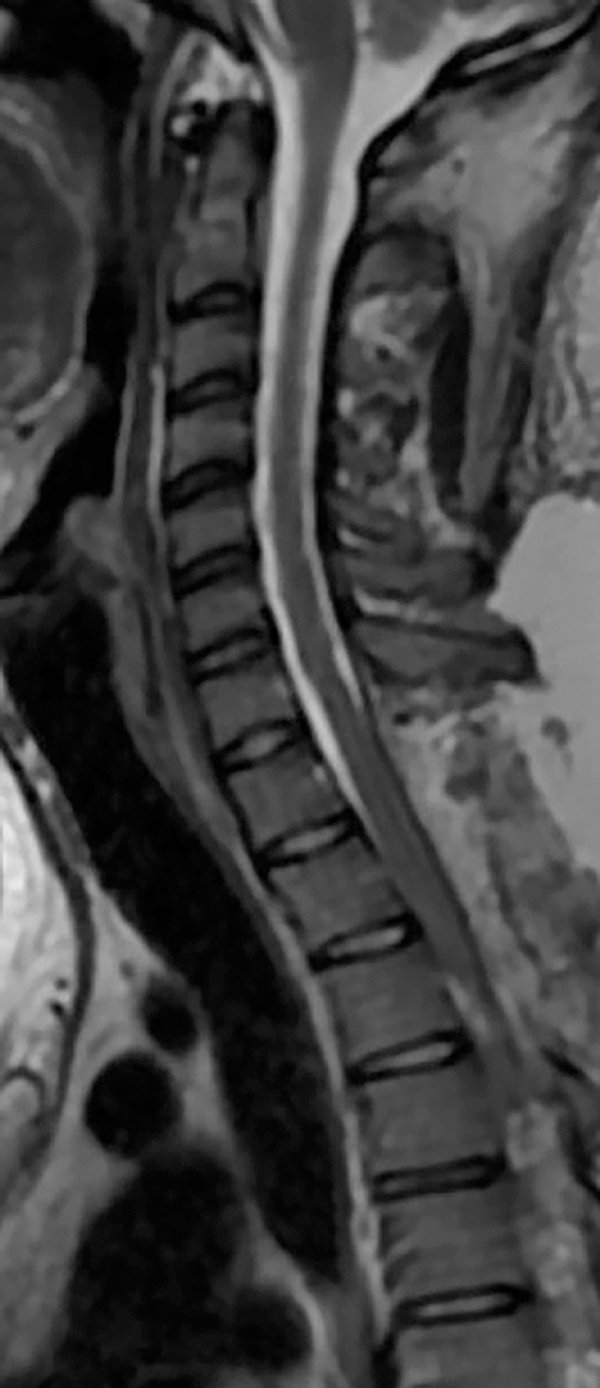

Se presenta el caso de una paciente de 21 años de edad, con antecedentes de infección por VIH, sífilis, consumo de drogas ilícitas y alcohol, que consulta por parestesias en ambos miembros inferiores de 6 meses de evolución, a lo que agrega paraparesia y dificultad en la marcha en los últimos 3 meses, con empeoramiento progresivo. Al examen físico presentaba una paraparesia moderada, hipertonía, hiperreflexia e hipoestesia en todas las modalidades sensitivas en miembros inferiores con nivel sensitivo T4 y signo de Babinski bilateral, así como también dolor dorsal con irradiación a ambos miembros inferiores. En la resonancia magnética (RMN) de columna completa se observaba una imagen a nivel T1 a T3, hipointensa en T1, hiperintensa en T2 y STIR, sin captación de contraste endovenoso, con desplazamiento posterior de la médula espinal y adelgazamiento de la misma (Figura 1 y 2). Se interpretó el cuadro como un quiste aracnoidal asociado a una aracnoiditis adhesiva. En este contexto, debido a la progresión y severidad de los síntomas, se realizó laminotomía T1-T2-T3 y evacuación de la lesión quística en el mismo nivel (Figura 3). Se enviaron muestras de aracnoides a anatomía patológica, la cual demostró “fragmento de tejido dural con fibroesclerosis y vasocongestión”; a su vez se realizaron cultivos de gérmenes comunes, hongos, parásitos, tuberculosis y PCRs virales, los cuales resultaron negativos.

La paciente evolucionó favorablemente desde el postoperatorio inmediato hasta la actualidad (4 meses posteriores), con mejoría parcial de la paraparesia y parestesias, y recuperación de la deambulación (Figura 4).

Figura 4: RMN en secuencia T2 de control postoperatorio, en donde se observa ausencia de la lesión quística y recuperación de la configuración habitual de la médula espinal.